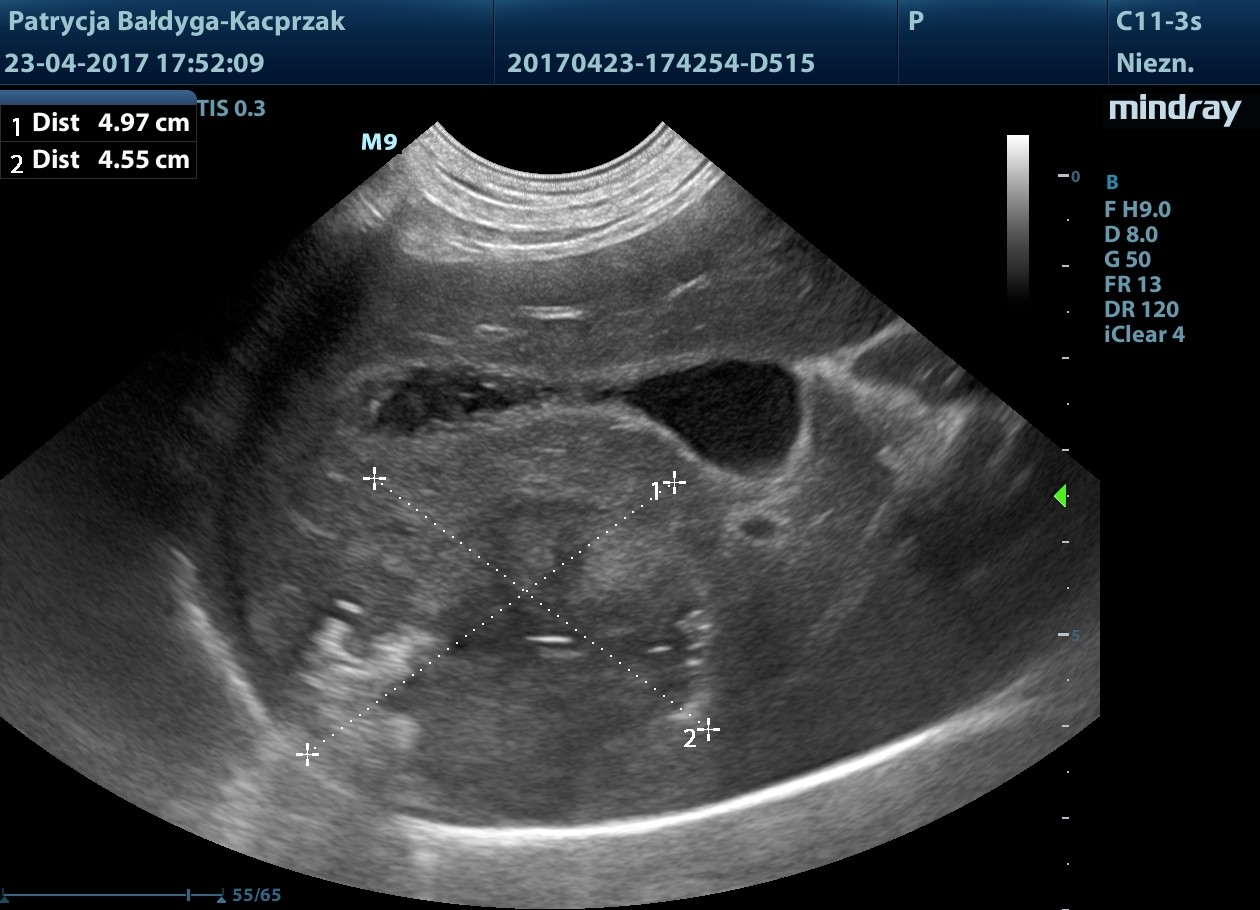

Maj

Widoczne nowe, liczne metastazy w wątrobie, niejednorodnie hiperechogenne, poszczególne wyglądu tarczy, śr. 1-5 cm, modulujące naczynia oraz brzegi narządu.

Czerwiec

W USG płyn w j. brzusznej w dużej ilości, decyzja o eutanazji, sekcja wykazała: krwotok z guzów wątroby